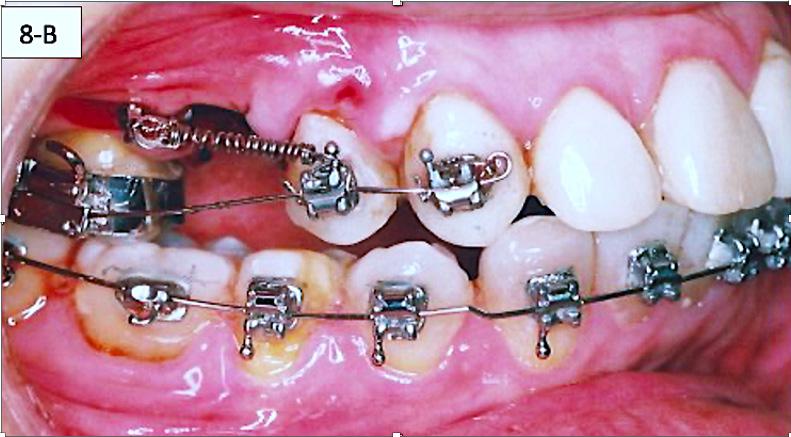

The brackets were bonded on maxillary cuspids, bicuspids and mandibular anterior teeth followed by placement of a 014 SS sectional wire in the maxilla and a .014 SS arch wire in the mandible. Maxillary second bicuspids were extracted, and a 1.6 x 8.0 mm AncorPro (OrthoOrganizers) TADs were inserted just mesially to the first molars. Closing coil springs were attached from the TADs to the first bicuspids (Regional Acceleratory Phenomenon) (Figure 8-A, B, C).7

FIG. 8A: Odontectomy of #15(4) & # 25(13)

FIG. 8B: CCS and TAD, right lateral view

FIG. 8C: CCS and TAD, left lateral view